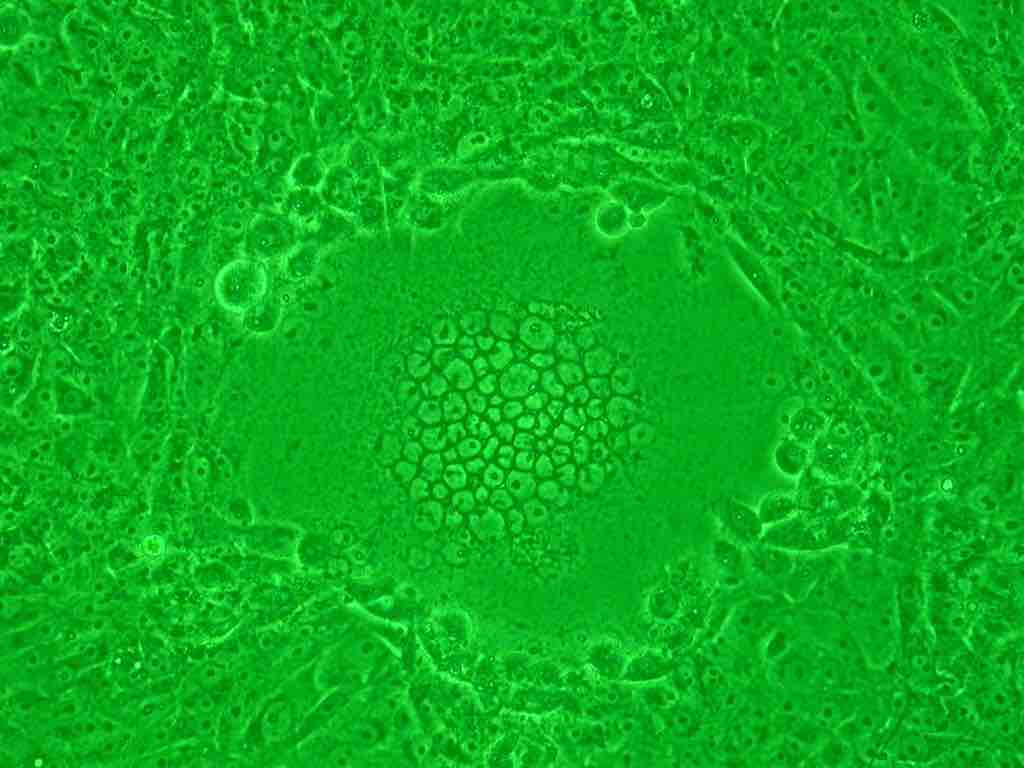

Syncytium

The mass or "ball" of cells in the middle of the image are a syncytium of cells that formed due to infection by the HIV virus.